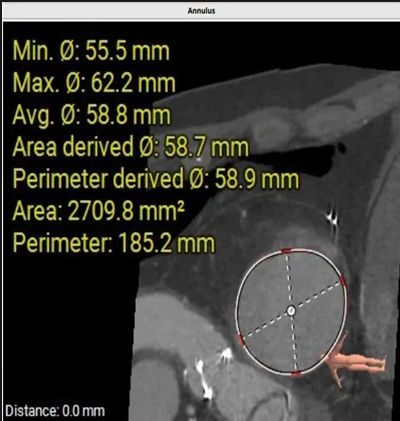

術(shù)前心臟CT評(píng)估

三尖瓣環(huán)平均周長(zhǎng)徑58.8mm,最大直徑62.2mm